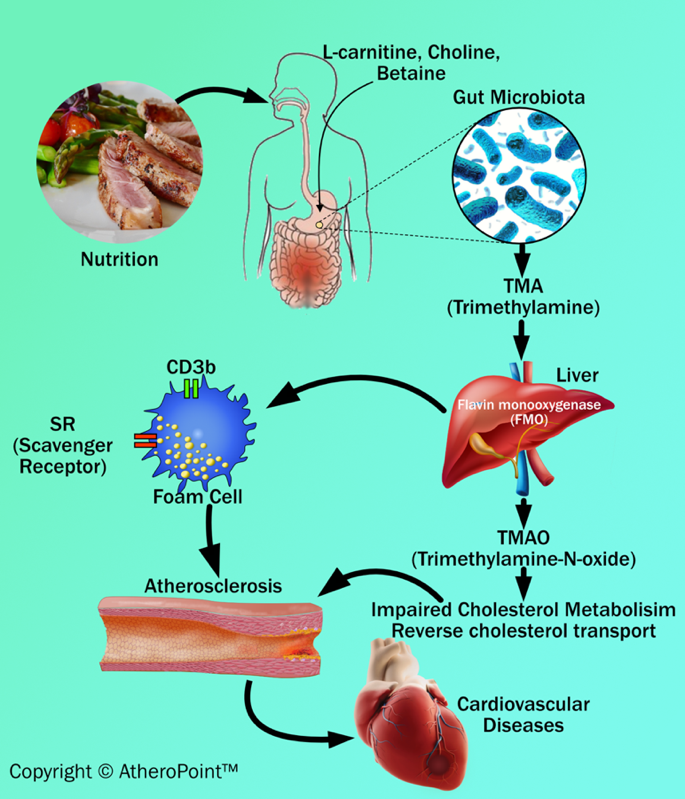

The pathophysiological link between nutrition and atherosclerosis

Animal dietary products increase the risk of atherosclerosis. Many recent articles show that dysbiosis (impaired microbiota) of intestinal microbes are linked with certain animal dietary products that can generate metabolites (intermediate products) like trimethylamine (TMA) and trimethylamine N-oxide levels (TMAO), which acts as key factors in developing atherosclerosis and results in cardiovascular diseases [94, 95, 96, 97] (see Fig. 5). Additionally, the recent clinical data has shown that TMA is formed from precursors like lecithin, choline, betaine, and L-carnitine. These are abundantly present in animal-based dietary components like meat, milk, and fish [96, 98, 99].

Fig. 5.

Fig. 5.Dietary adulteration and atherosclerosis development.

TMA is an organic compound produced from dietary quaternary amine components (i.e., L-carnitine and choline) by gut microbiota. Further, TMA is subsequently oxidized by hepatic flavin monooxygenase (FMO) to form TMAO in the liver [93]. TMAO can cause inflammatory reactions of the vascular wall by (i) increasing reactive oxygen species production, (ii) impairing cholesterol metabolism, and (iii) increasing sterol metabolism. These three, when combined, are involved in the formation of plaque in the blood vessel [100]. In addition to an impact on cholesterol and sterol metabolism, TMAO also increases the expression of scavenger receptors such as CD36 and scavenger receptor type 1 on the surface of macrophages. This results in a decrease in reverse cholesterol transport and promotes foam cell formation. Foam cells are also known as lipid-laden macrophages that contain cholesterol inside. In abundance, they can result in the formation of plaque that initiates the progression of atherosclerosis and triggers cardiovascular diseases [96, 98].